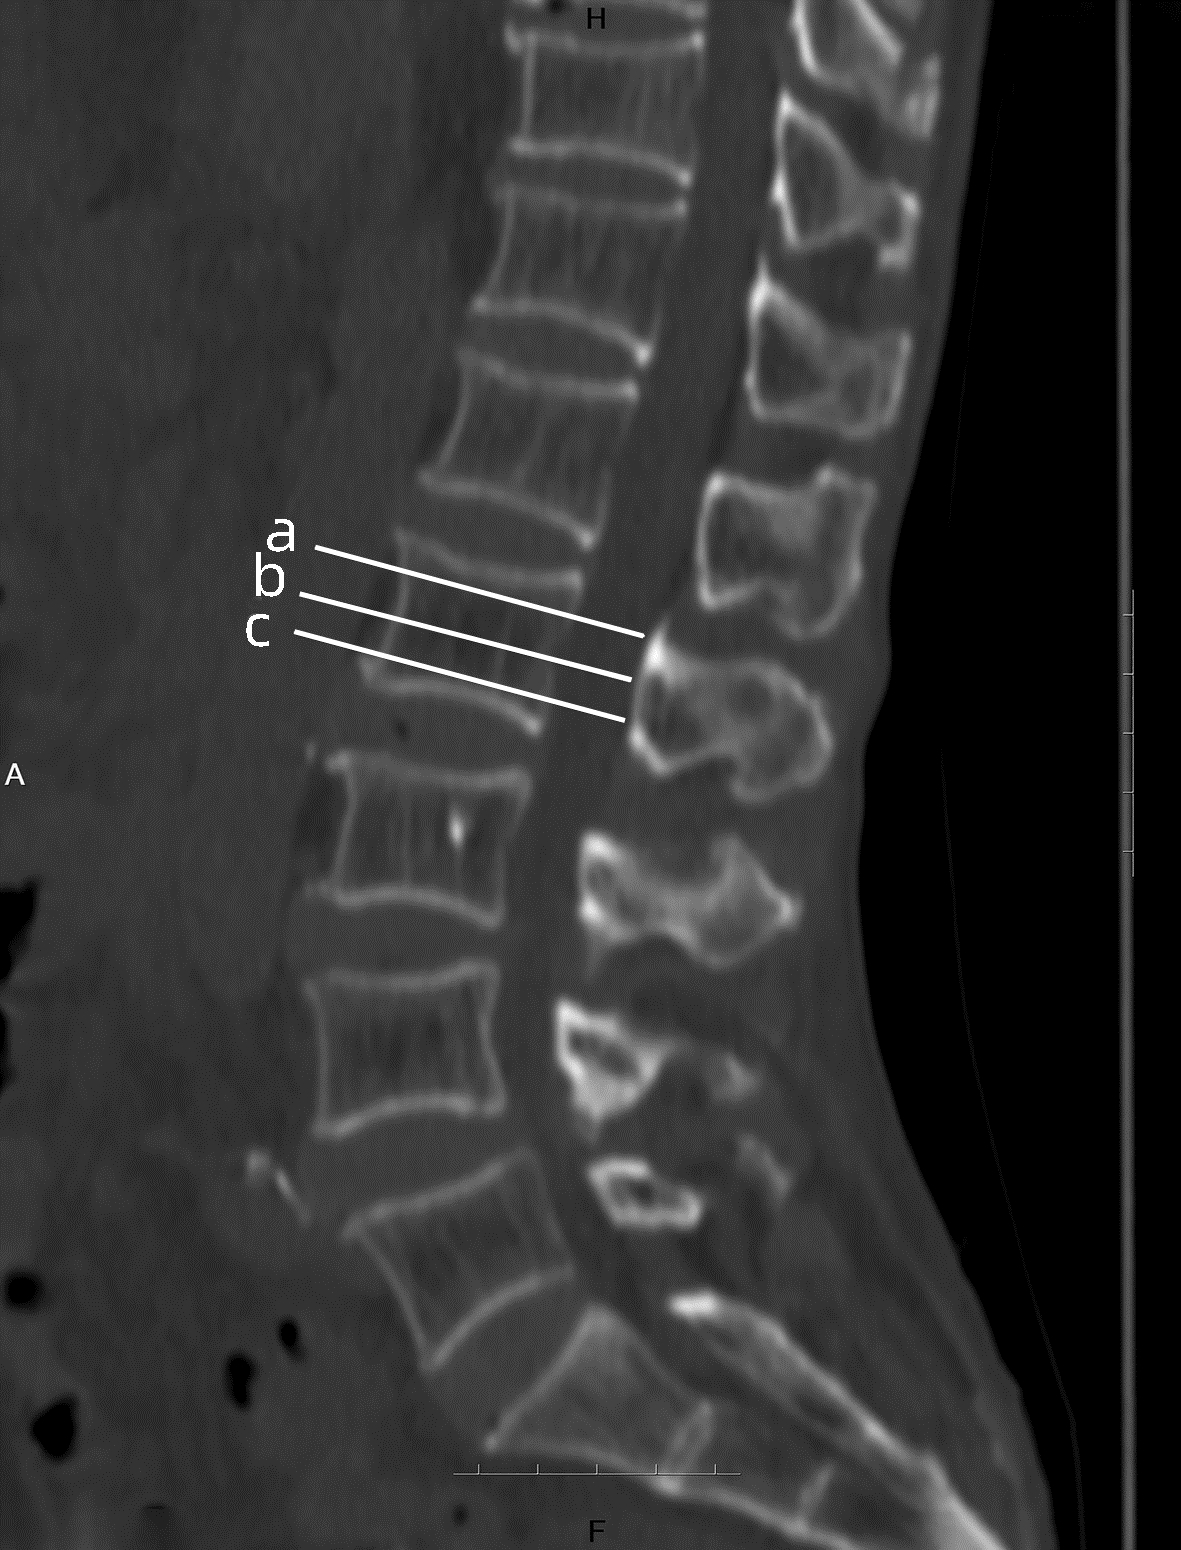

目的  评价在慢性乙型肝炎患者腹部CT中通过测量胸、腰椎CT值,诊断骨量减少/骨质疏松的诊断价值。分析慢性乙型肝炎患者发生骨量减少/骨质疏松的危险因素。  方法  回顾性纳入2019年1月—2020年12月在昆明医科大学第二附属医院就诊的慢性乙型肝炎患者112例,所有患者均完善了腹部CT检查,部分患者完善了双能X线骨密度测定(DXA)。测量T12椎体至L3椎体的CT值,分析每一椎体CT值与DXA检查基于L1~L4椎体测得的T-score值相比诊断骨量减少/骨质疏松的诊断价值。以椎体CT值为诊断标准,将纳入的慢性乙型肝炎患者分为骨量减少/骨质疏松组(n=55)与骨量正常组(n=57),对比两组患者临床特征、生化指标,分析慢性乙型肝炎患者发生骨量减少/骨质疏松的危险因素。符合正态分布的计量资料两组间比较采用t检验;非正态分布的计量资料两组间比较采用Mann-Whitney U检验。计数资料组间比较采用χ2检验、Fisher确切检验、Bonferroni校正检验。相关性采用Pearson相关分析。多因素分析采用二元logistic回归分析。根据受试者工作特征曲线(ROC曲线)评估T12~L3椎体CT值诊断慢性乙型肝炎患者合并骨量减少/骨质疏松的诊断价值。一致性检验采用Kappa检验。  结果  分析46例在同次住院中完善了腹部CT和DXA检查患者的T12~L3椎体CT值,均分别与DXA检查结果中基于L1~L4椎体计算的T-score值有显著正相关性(rT12=0.694,rL1=0.661,rL2=0.781,rL3=0.685,P值均<0.001);经ROC曲线分析,L2椎体CT值ROC曲线下面积最大(0.863),诊断骨量减少/骨质疏松具有较好准确性,与DXA检查结果具有较好一致性(K=0.648,P<0.001)。分析112例慢性乙型肝炎患者临床特征、生化指标,提示高龄(比值比为1.108,95%CI:1.026~1.196,P=0.009)、合并肌少症(比值比为2.788,95%CI:1.009~7.707,P=0.048) 是骨量减少/骨质疏松发生的危险因素。  结论  慢性乙型肝炎患者常需定期复查腹部CT评估肝脏疾病进展情况,通过测量患者腹部CT图像中L2椎体CT值、L3椎体层面骨骼肌面积筛查是否存在骨量减少/骨质疏松、肌少症,及时干预,提高患者的预后、生活质量,具有较高临床意义。